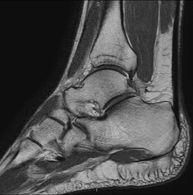

Exploració per estudiar aquesta articulació i les lesions freqüents de lligaments (esquinços), així com l'afectació d'altres estructures, com el cartílag o l'os. També és de gran utilitat per diagnosticar alteracions al tendó d'Aquil·les (tendinitis o trencaments). La durada aproximada és de 20 minuts. No utilitza radiació ionitzant. - RM de Peu

Exploració per a l'estudi de les lesions en petites estructures anatòmiques de l'articulació que solen produir-se en pacients que pateixen luxació o inestabilitat crònica. L'estudi ve precedit per una injecció de contrast a l'interior de l'articulació, realitzada sota control de raigs X. La durada total dels dos procediments és de 50 minuts.